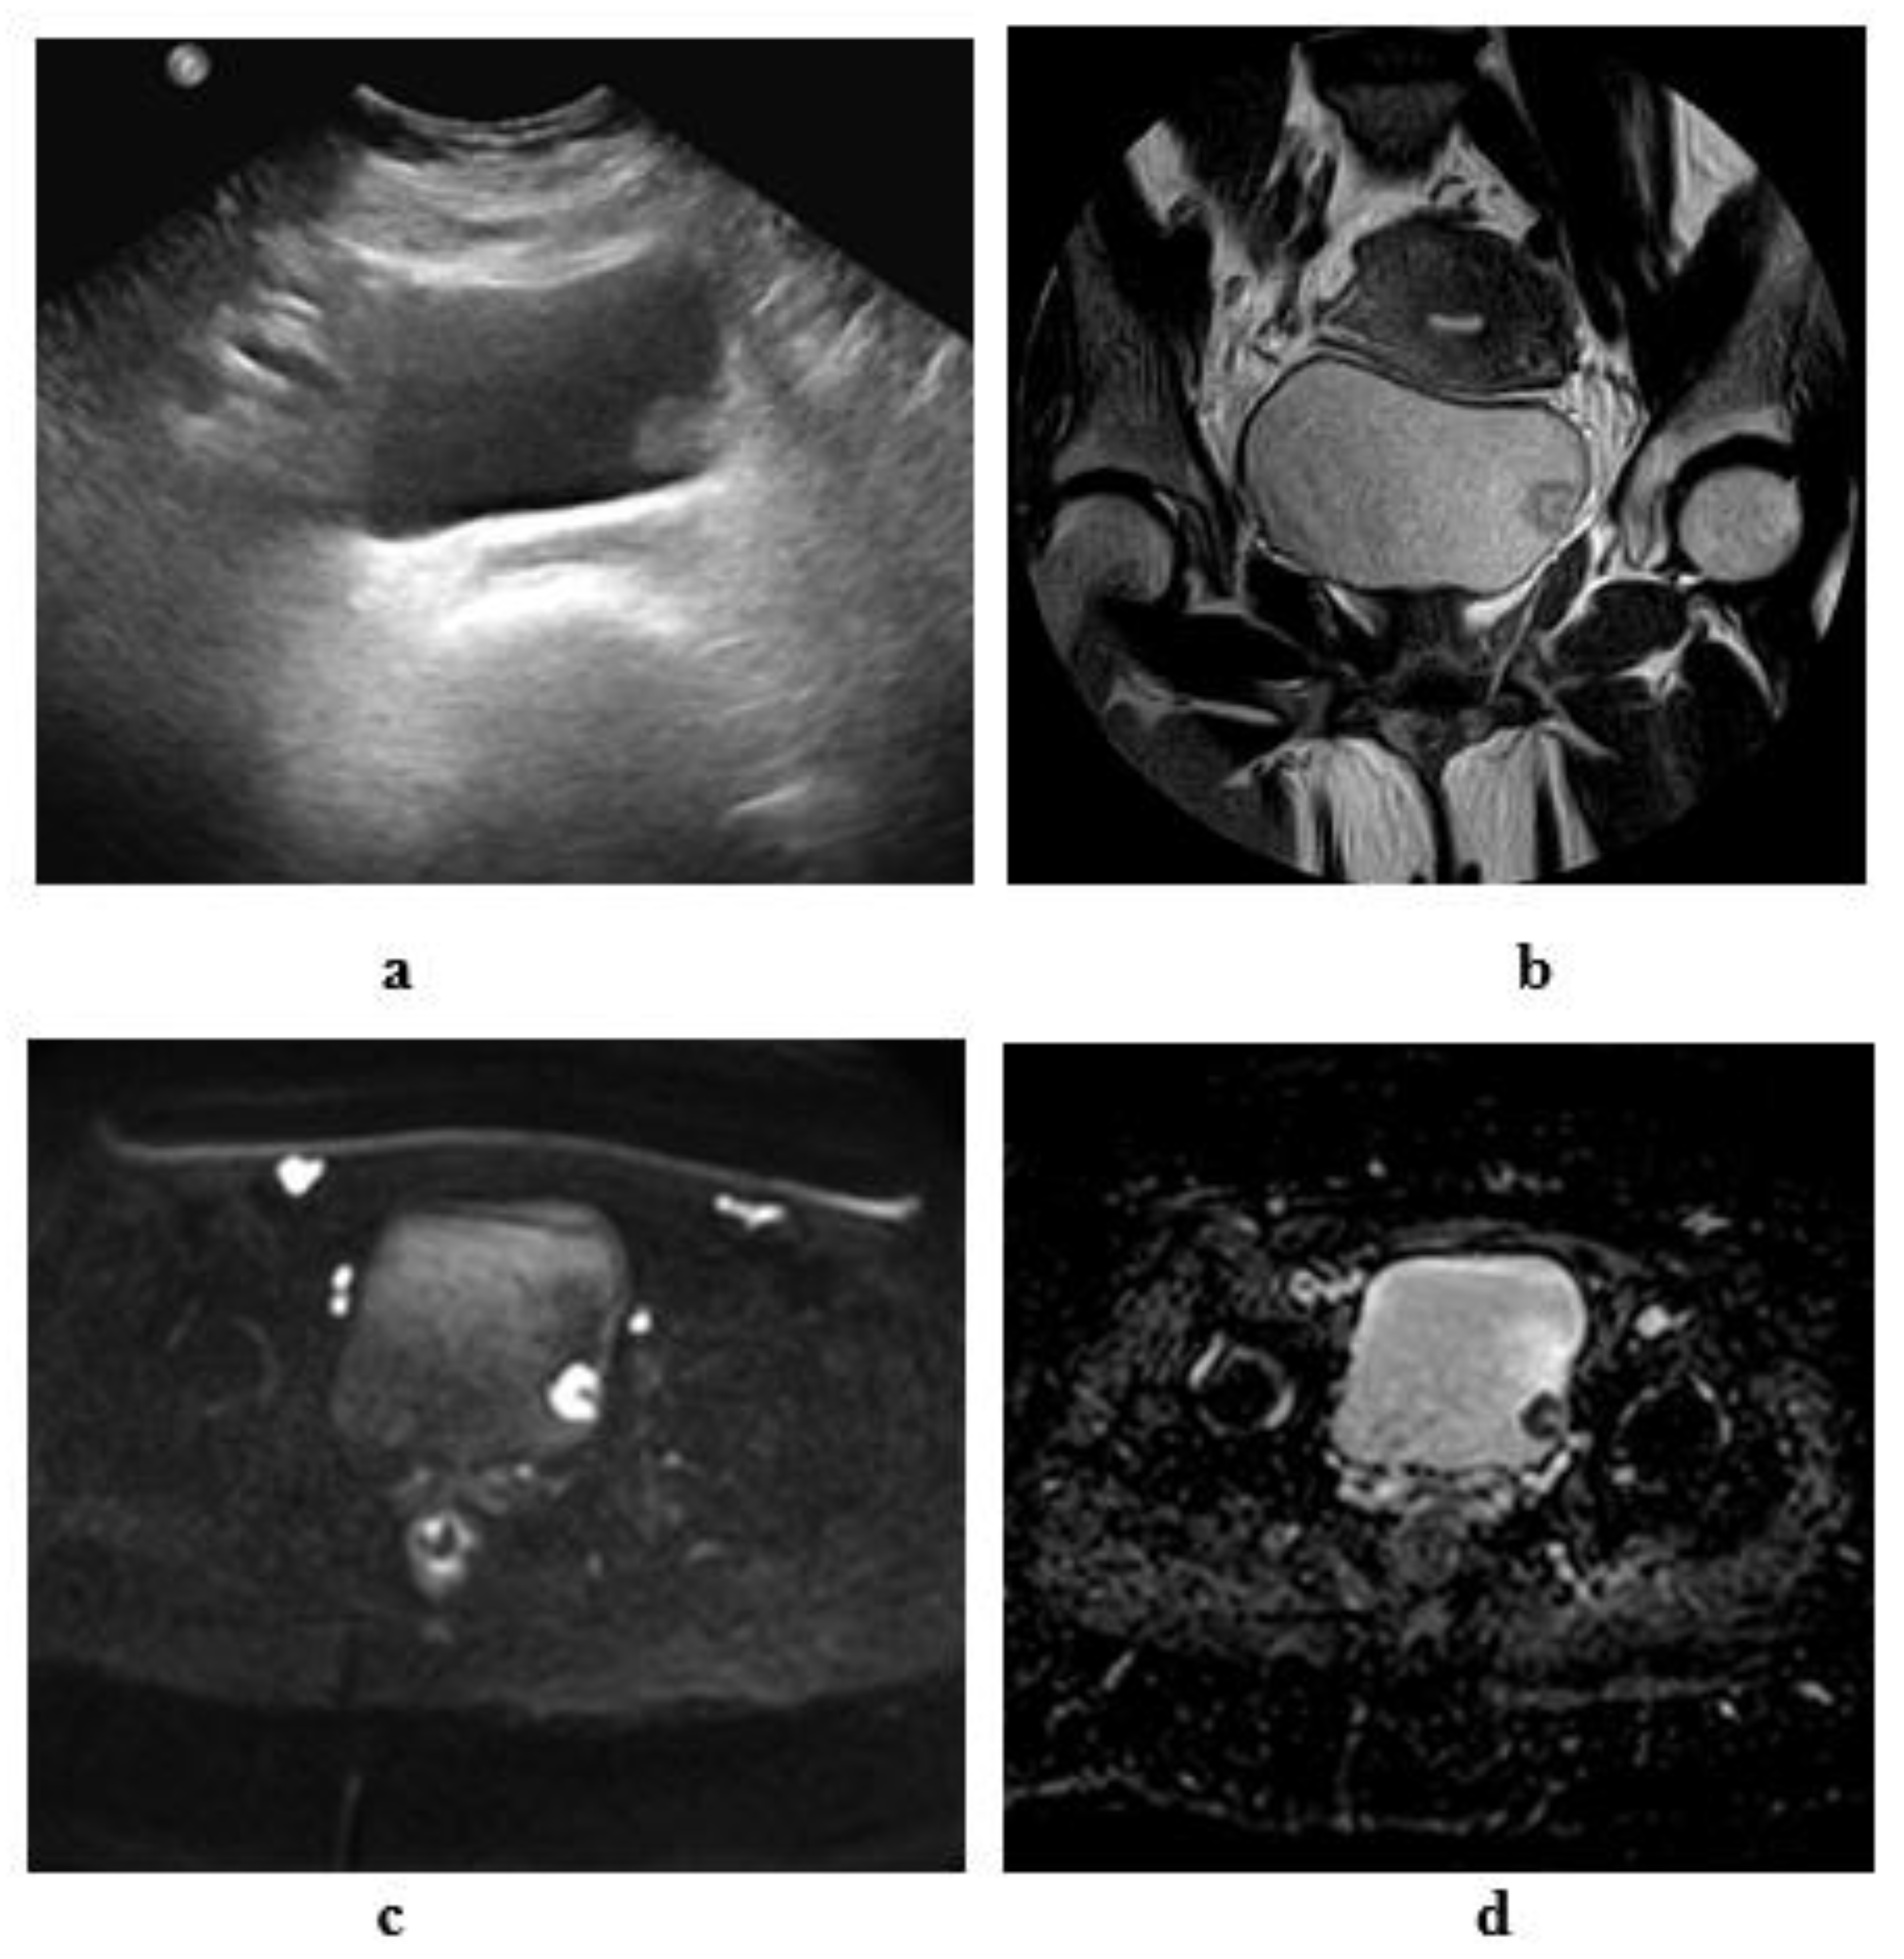

2.3. Ultrasonography

2.3.1. Conventional Ultrasonography

2.6. Magnetic Resonance Imaging

2.6.1. High-Resolution T2-Weighted Imaging (T2WI)

2.6.2. Diffusion-Weighted Imaging (DWI)

2.6.3. Dynamic Contrast-Enhanced (DCE) Imaging